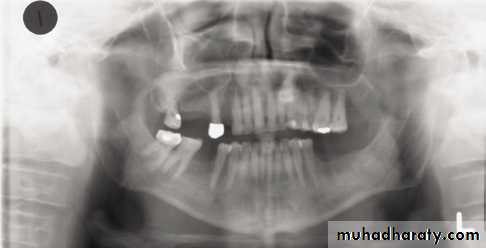

In a good panoramic radiograph:

The mandible is “U” shaped.

The condyles are positioned about equal distance from the inside edges of the image and 1⁄3 of the way down from the top edge of the image.

The occlusal plane exhibits a slight curve or “smile line,” upwards.

The roots of the maxillary and mandibular anterior teeth are readily visible with minimal distortion.

Magnification is equal on both sides of the midline.